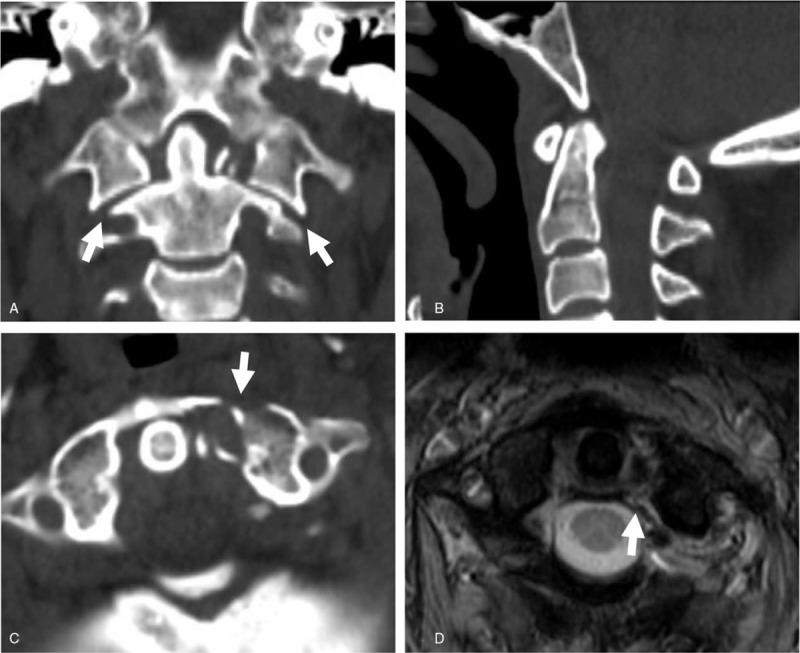

Unilateral sagittal split fracture (USSF) of the C1 lateral mass (LM) has been recently recognized as a rare variant of C1 atlas fracture. To date, there has been no study to investigate whether radiologic criteria can be applied to determine the presence or absence of transverse atlantal ligament (TAL) injury in USSF of the C1 LM.Twenty six consecutive cases of USSF of the C1 LM were included in this study. According to Dickman classification, 16 cases were TAL injury, and 10 cases were TAL intact. Radiologic parameters were measured and compared between the 2 groups.Total LM displacement (LMD) of the 2 sides (5.9 ± 2.0 mm vs 1.2 ± 2.0 mm), unilateral LMD of the fracture side (4.3 ± 1.2 mm vs 1.0 ± 1.1 mm), atlanto-dental interval (ADI) (2.0 ± 0.9 mm vs 1.5 ± 0.4 mm), and fracture gap (6.9 ± 2.7 mm vs 2.1 ± 1.1 mm) were statistically higher in the TAL injury group than the TAL intact group. However, basion-dental interval, clivus canal angle, and atlanto-occipital joint axis angle were not different between the 2 groups. Total LMD and unilateral LMD positively correlated with ADI and fracture gap. The incidence of fracture gap larger than 7 mm was statistically higher in the TAL injury group than the TAL intact group (81% vs 30%).In conclusion, total LMD > 5.9 mm or unilateral LMD > 4.3 mm suggests the presence of TAL injury in USSF of the C1 LM. The possibility of diagnostic error for TAL injury can be further reduced in USSF of the C1 LM by considering the fracture gap larger than 7 mm.

寰椎侧块单侧矢状劈裂骨折(USSF)最近被认为是寰椎骨折的一种罕见类型。迄今为止,尚无研究探讨影像学标准是否可用于判断C1侧块USSF中寰椎横韧带(TAL)损伤的有无。本研究纳入了26例连续的C1侧块USSF病例。根据迪克曼分类,16例为TAL损伤,10例为TAL完整。对两组的影像学参数进行测量和比较。TAL损伤组两侧的总侧块移位(LMD)(5.9±2.0mm对1.2±2.0mm)、骨折侧的单侧LMD(4.3±1.2mm对1.0±1.1mm)、寰齿间距(ADI)(2.0±0.9mm对1.5±0.4mm)和骨折间隙(6.9±2.7mm对2.1±1.1mm)在统计学上均高于TAL完整组。然而,两组之间的颅底齿突间距、斜坡管角度和寰枕关节轴角度并无差异。总LMD和单侧LMD与ADI和骨折间隙呈正相关。TAL损伤组骨折间隙大于7mm的发生率在统计学上高于TAL完整组(81%对30%)。总之,总LMD>5.9mm或单侧LMD>4.3mm提示C1侧块USSF中存在TAL损伤。通过考虑骨折间隙大于7mm,可进一步降低C1侧块USSF中TAL损伤的诊断错误可能性。